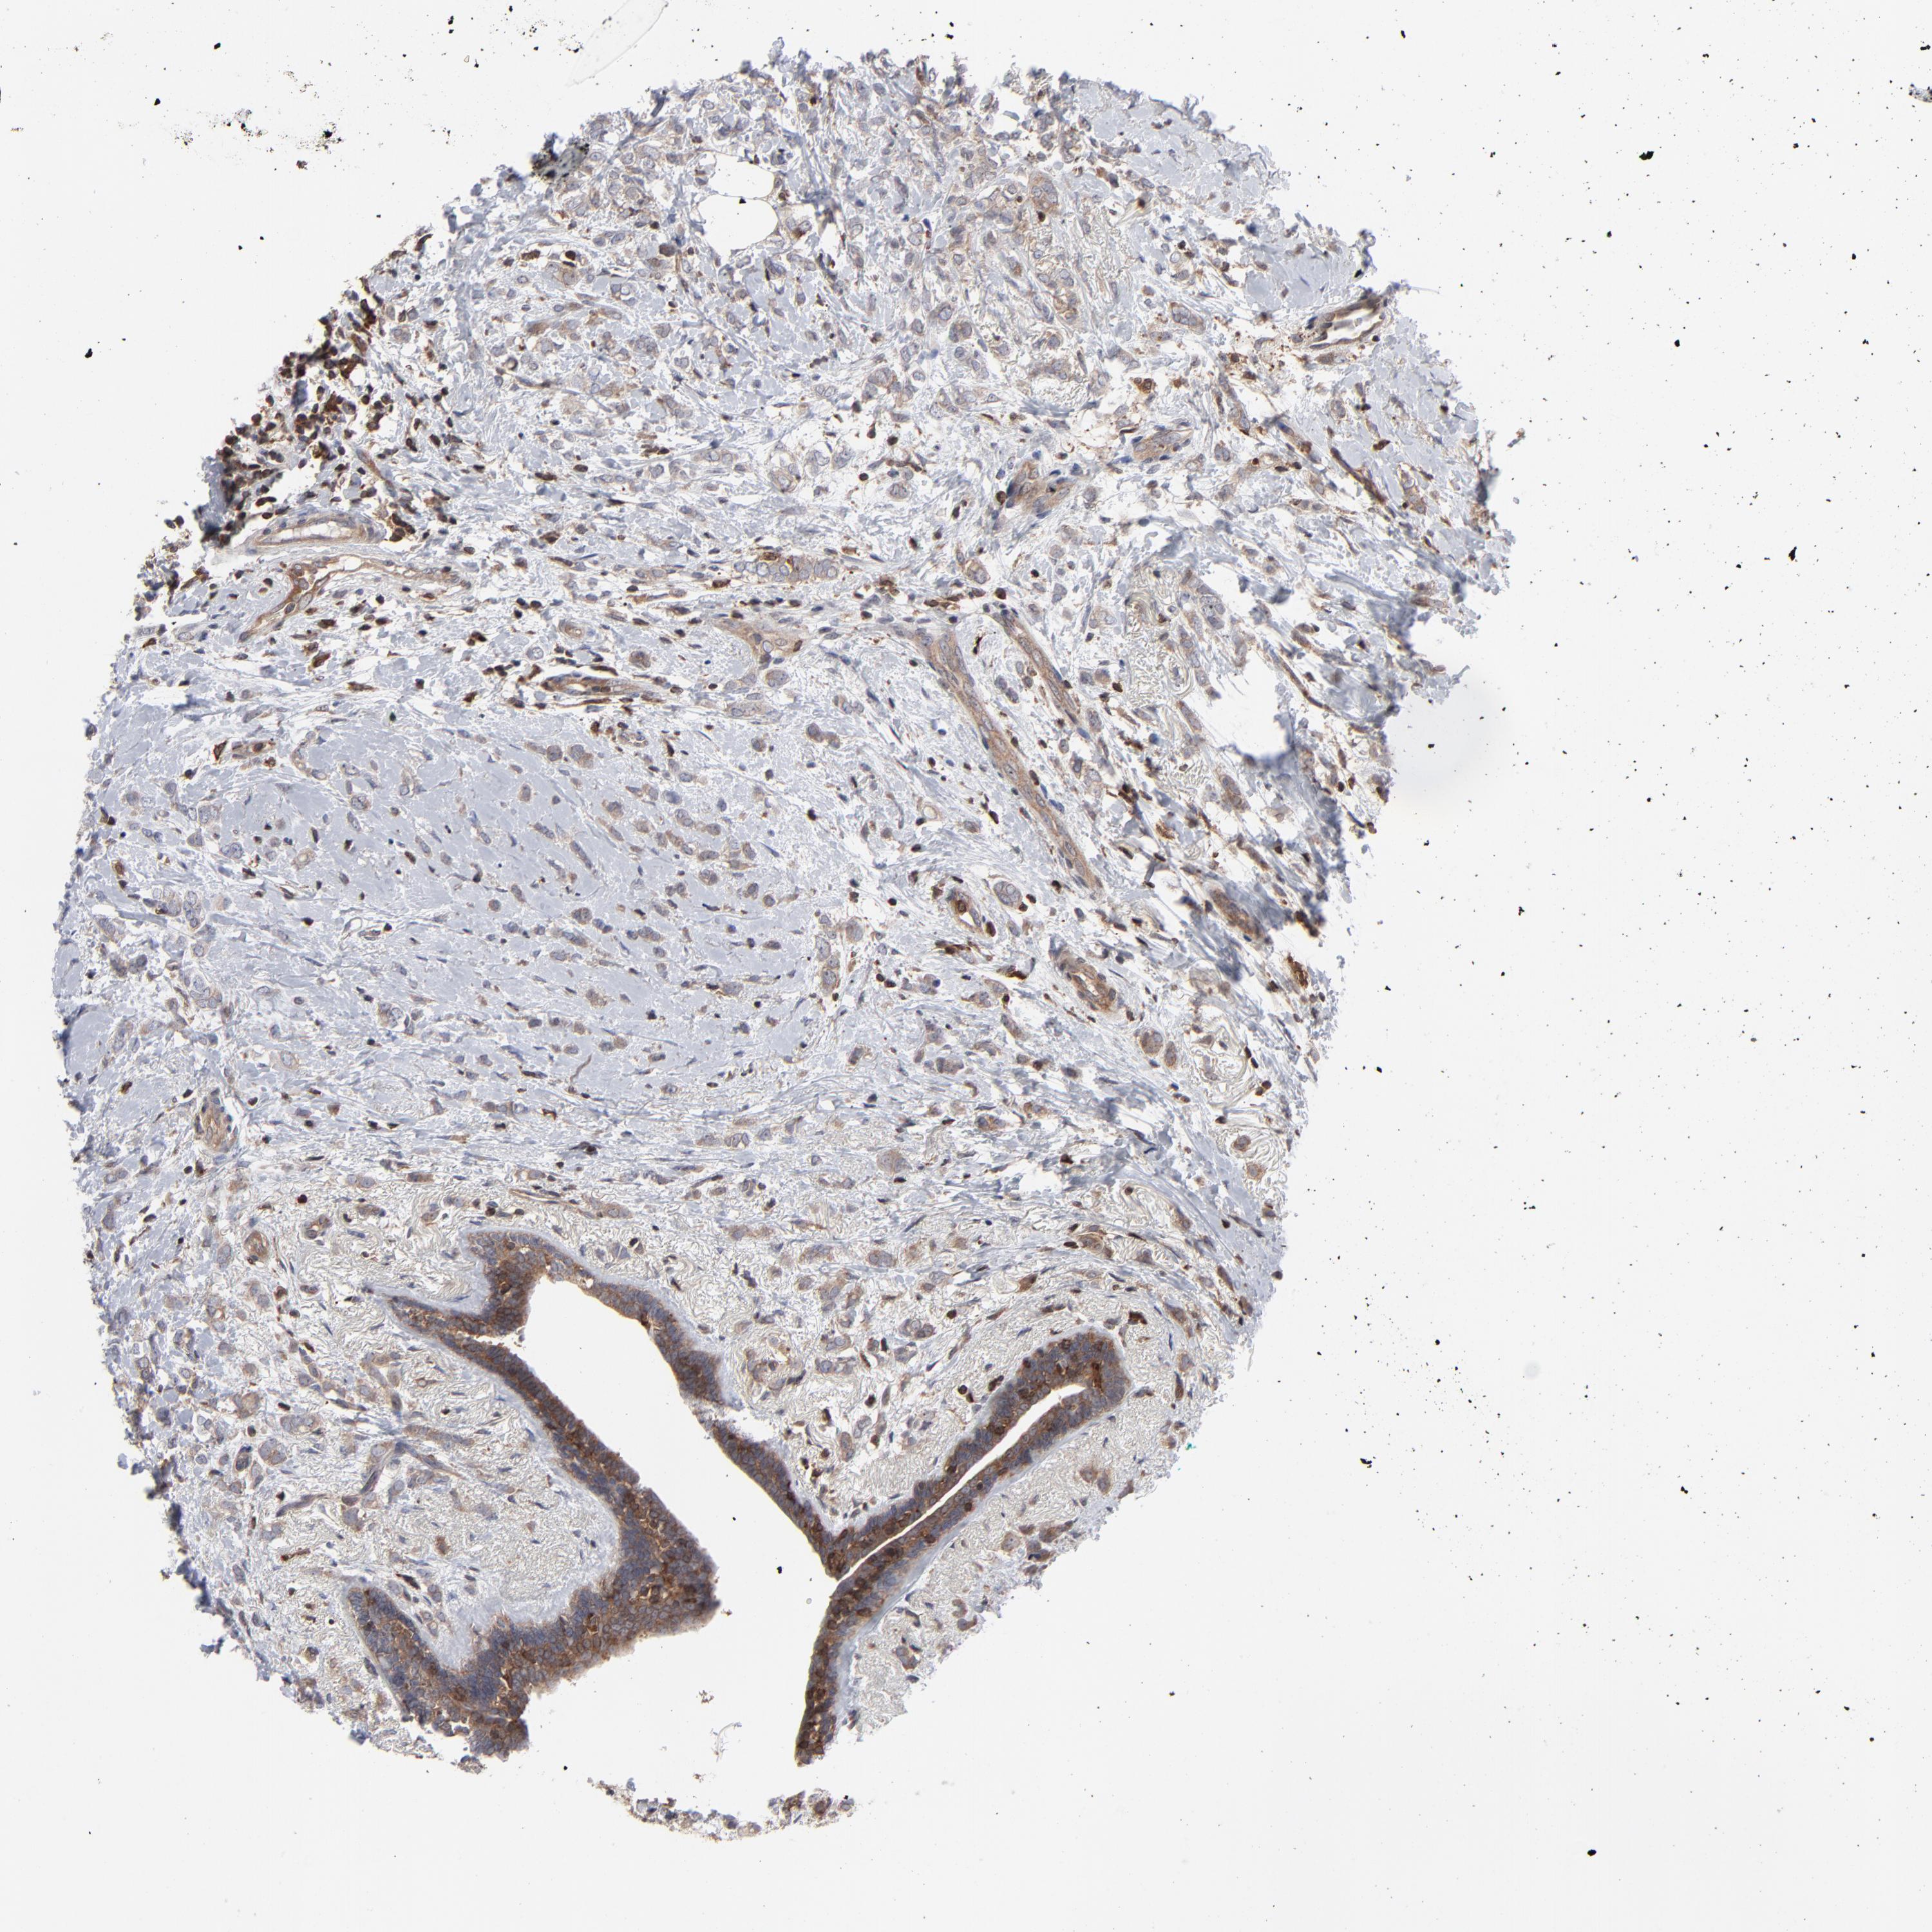

CANCER BREAST CANCER Show tissue menu

BRCA TCGA BRCA VALIDATION PROTEIN EXPRESSION